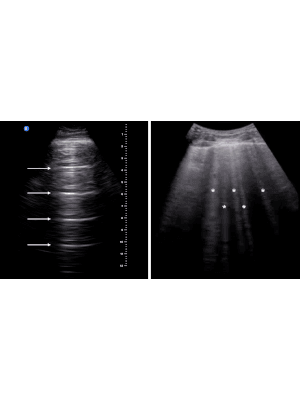

Use of point-of-care ultrasound (POCUS) as a tool aims to offer improved diagnostic accuracy at the bedside in real-time, often obviating the need for a subsequent departmental examination. If done correctly, this has the potential to reduce the demands on radiology services. For this to be the case, two conditions need to be met: the first is that POCUS needs to demonstrate a diagnostic accuracy that is acceptable; and the second is that those images and reports need to be available for review, quality assurance and subsequent audit if required.